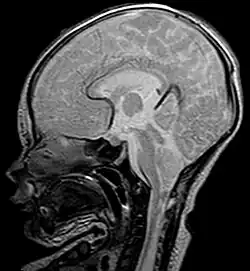

Als Chiari-Malformation wird eine Gruppe von Entwicklungsstörungen mit Verschiebung von Kleinhirnanteilen durch das Hinterhauptloch (Foramen magnum) in den Spinalkanal bei gleichzeitig bestehender verkleinerter hinterer Schädelgrube bezeichnet. Namensgeber ist der Pathologe Hans Chiari (1851–1916), der diese Störung erstmals beschrieb.[1] Die Bezeichnungen Arnold-Chiari-Malformation und Arnold-Chiari-Syndrom wurden von den Schülern des Pathologen Julius Arnold (1835–1915) propagiert, scheinen aber nicht gerechtfertigt, weil diese Gruppe der Entwicklungsstörungen von Arnold nur oberflächlich beschrieben wurde.[2]

- Typ I: Hier liegt eine Verlagerung der Kleinhirntonsillen vor. Als Komplikation kann es zu einer Syringomyelie kommen. Seltener werden knöcherne Fehlbildungen des Schädelbodens und der Wirbelkörper beobachtet. Patienten können durchaus beschwerdefrei sein.[3] Beschwerden treten nicht selten erst im jungen Erwachsenenalter auf. Neben Kopf- und Nackenschmerzen können dies z. B. Zeichen einer Schädigung des Kleinhirns, (z. B. eine als Ataxie bezeichnete Gangunsicherheit) oder des Hirnstamms (z. B. Schluckstörungen) sein. Chiari Typ I Malformationen können bei Patienten mit Ehlers-Danlos Syndrom vorkommen.[4]

- Typ II: Hier kommt es zu einer ausgeprägteren Verlagerung des Kleinhirnwurmes kombiniert mit Kompression und Verlagerung des Hirnstammes sowie Verlagerung des vierten Ventrikels mit Entwicklung eines Hydrozephalus. Normalerweise treten knöcherne Fehlbildungen mit Ausbildung einer Myelomeningeozele hinzu. Der Begriff Arnold-Chiari-Malformation bezieht sich nur auf diese Unterform der Chiari-Malformation.[5]

Die Diagnosestellung erfolgt kernspintomographisch. Bei Feten können das so genannte Lemon sign oder Banana sign als sonografische Softmarker in der pränataldiagnostischen Sonografie ein möglicher Hinweis auf eine Chiari-Malformation sein.